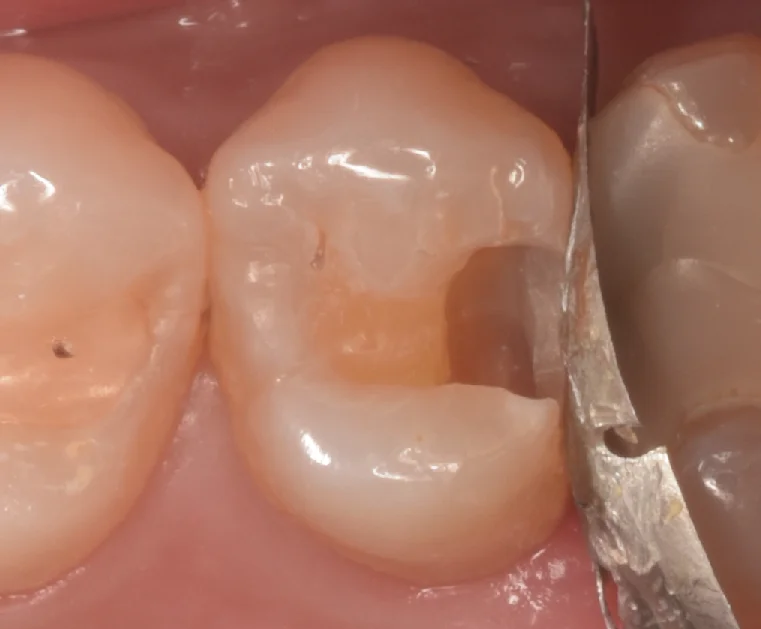

隣の歯との間に入れている金属の板は、隣の歯を保護するためのものになります。

少しでも掠って微細な傷でもつけようものなら、今回のように後々新しい虫歯ができたりしますからね・・・。

これ自体は保険自費問わず、必要なケースでは必ず使用するようにしています。

今回は隣が人工物なので不要と言う考え方もありますが、私としては人工物にも段差ができ、細菌繁殖されると困るので、どっちにしろ危ない時は使うようにしてます。